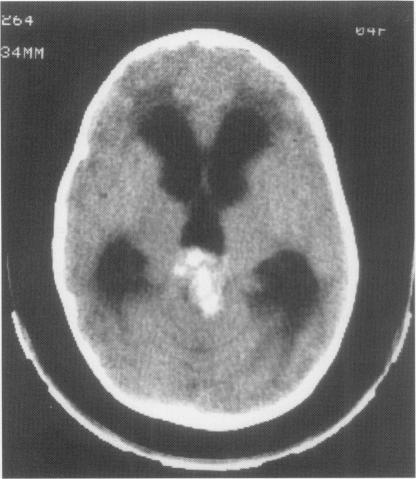

The RB1 gene mutation was investigated in a child with ectopic intracranial retinoblastoma using DNA obtained from both the pineal and retinal tumours of the patient. A nonsense mutation in exon 17 (codon 556) of the RB1 gene was found to be present homozygously in both the retinal and the pineal tumours. The same mutation was present heterozygously in the DNA from the constitutional cells of the patient, proving it to be of germline origin. The initial mutation was shown to have occurred in the paternally derived RB1 allele. The mutation is in an area of the gene that encodes the protein-binding region known as the 'pocket' region and has been detected in other cases of retinoblastoma.

利用从一名患有异位颅内视网膜母细胞瘤患儿的松果体瘤和视网膜肿瘤中获取的DNA,对RB1基因突变进行了研究。发现RB1基因第17外显子(密码子556)中的一个无义突变在视网膜肿瘤和松果体瘤中均为纯合存在。在该患者的体细胞DNA中,相同的突变以杂合形式存在,证明其起源于种系。最初的突变显示发生在父源的RB1等位基因中。该突变位于基因中编码被称为“口袋”区域的蛋白质结合区,并且在其他视网膜母细胞瘤病例中也有检测到。